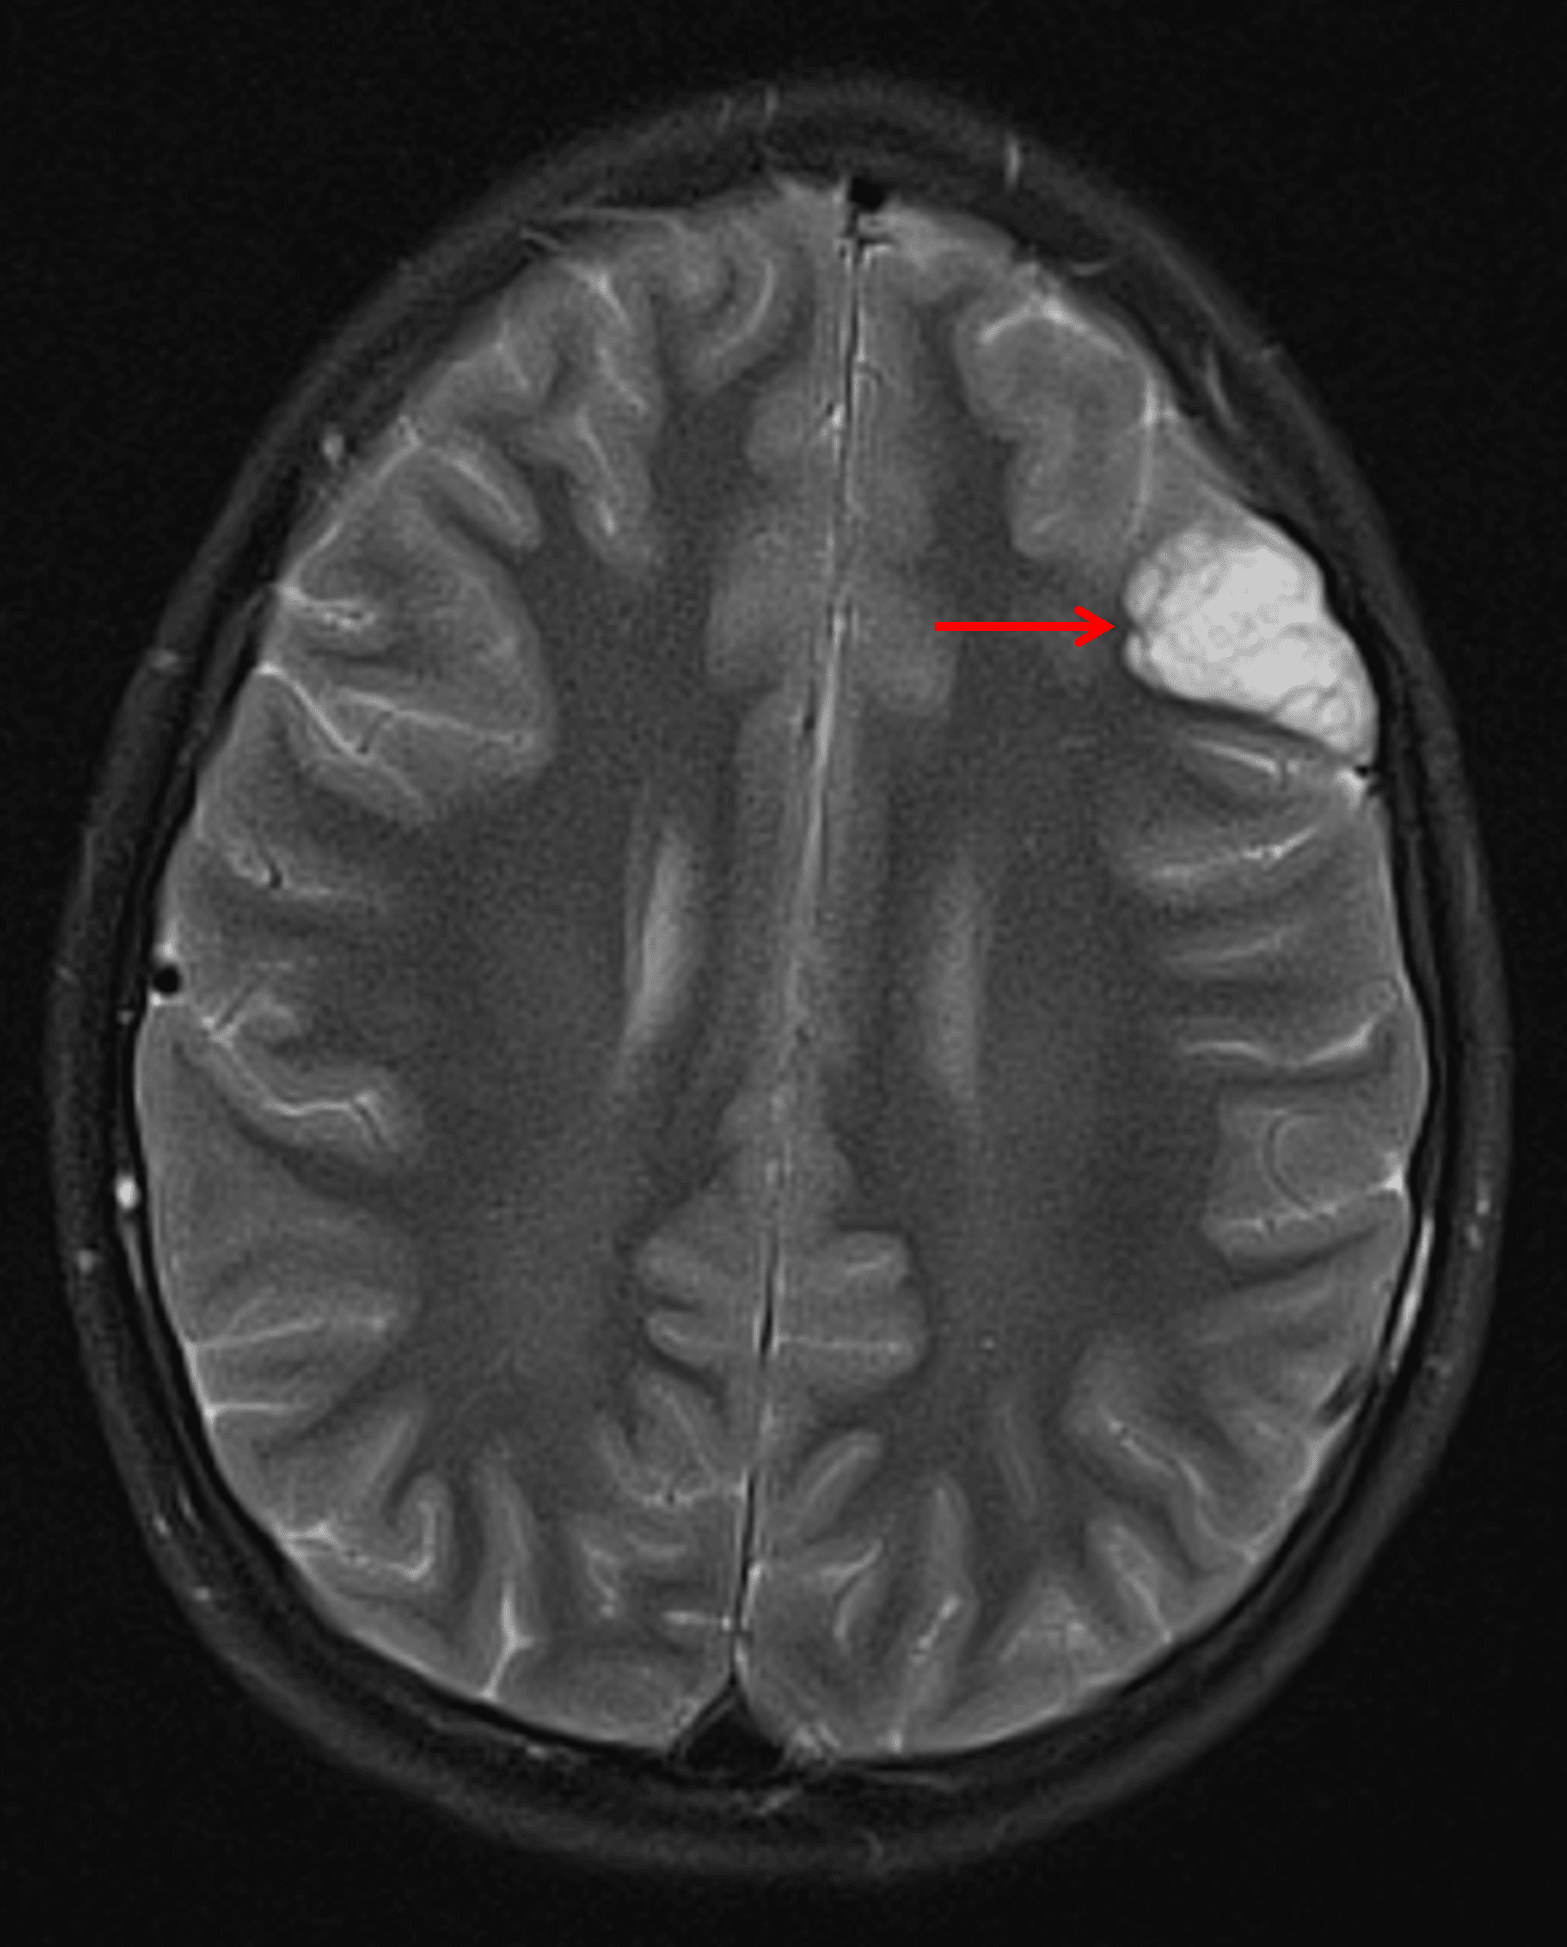

Wedge-shaped, cortically-based, bubbly T2 hyperintense lesion in the left frontal lobe (red arrow) consistent with a DNET.

Dysembryoplastic neuroepithelial tumor (DNET)